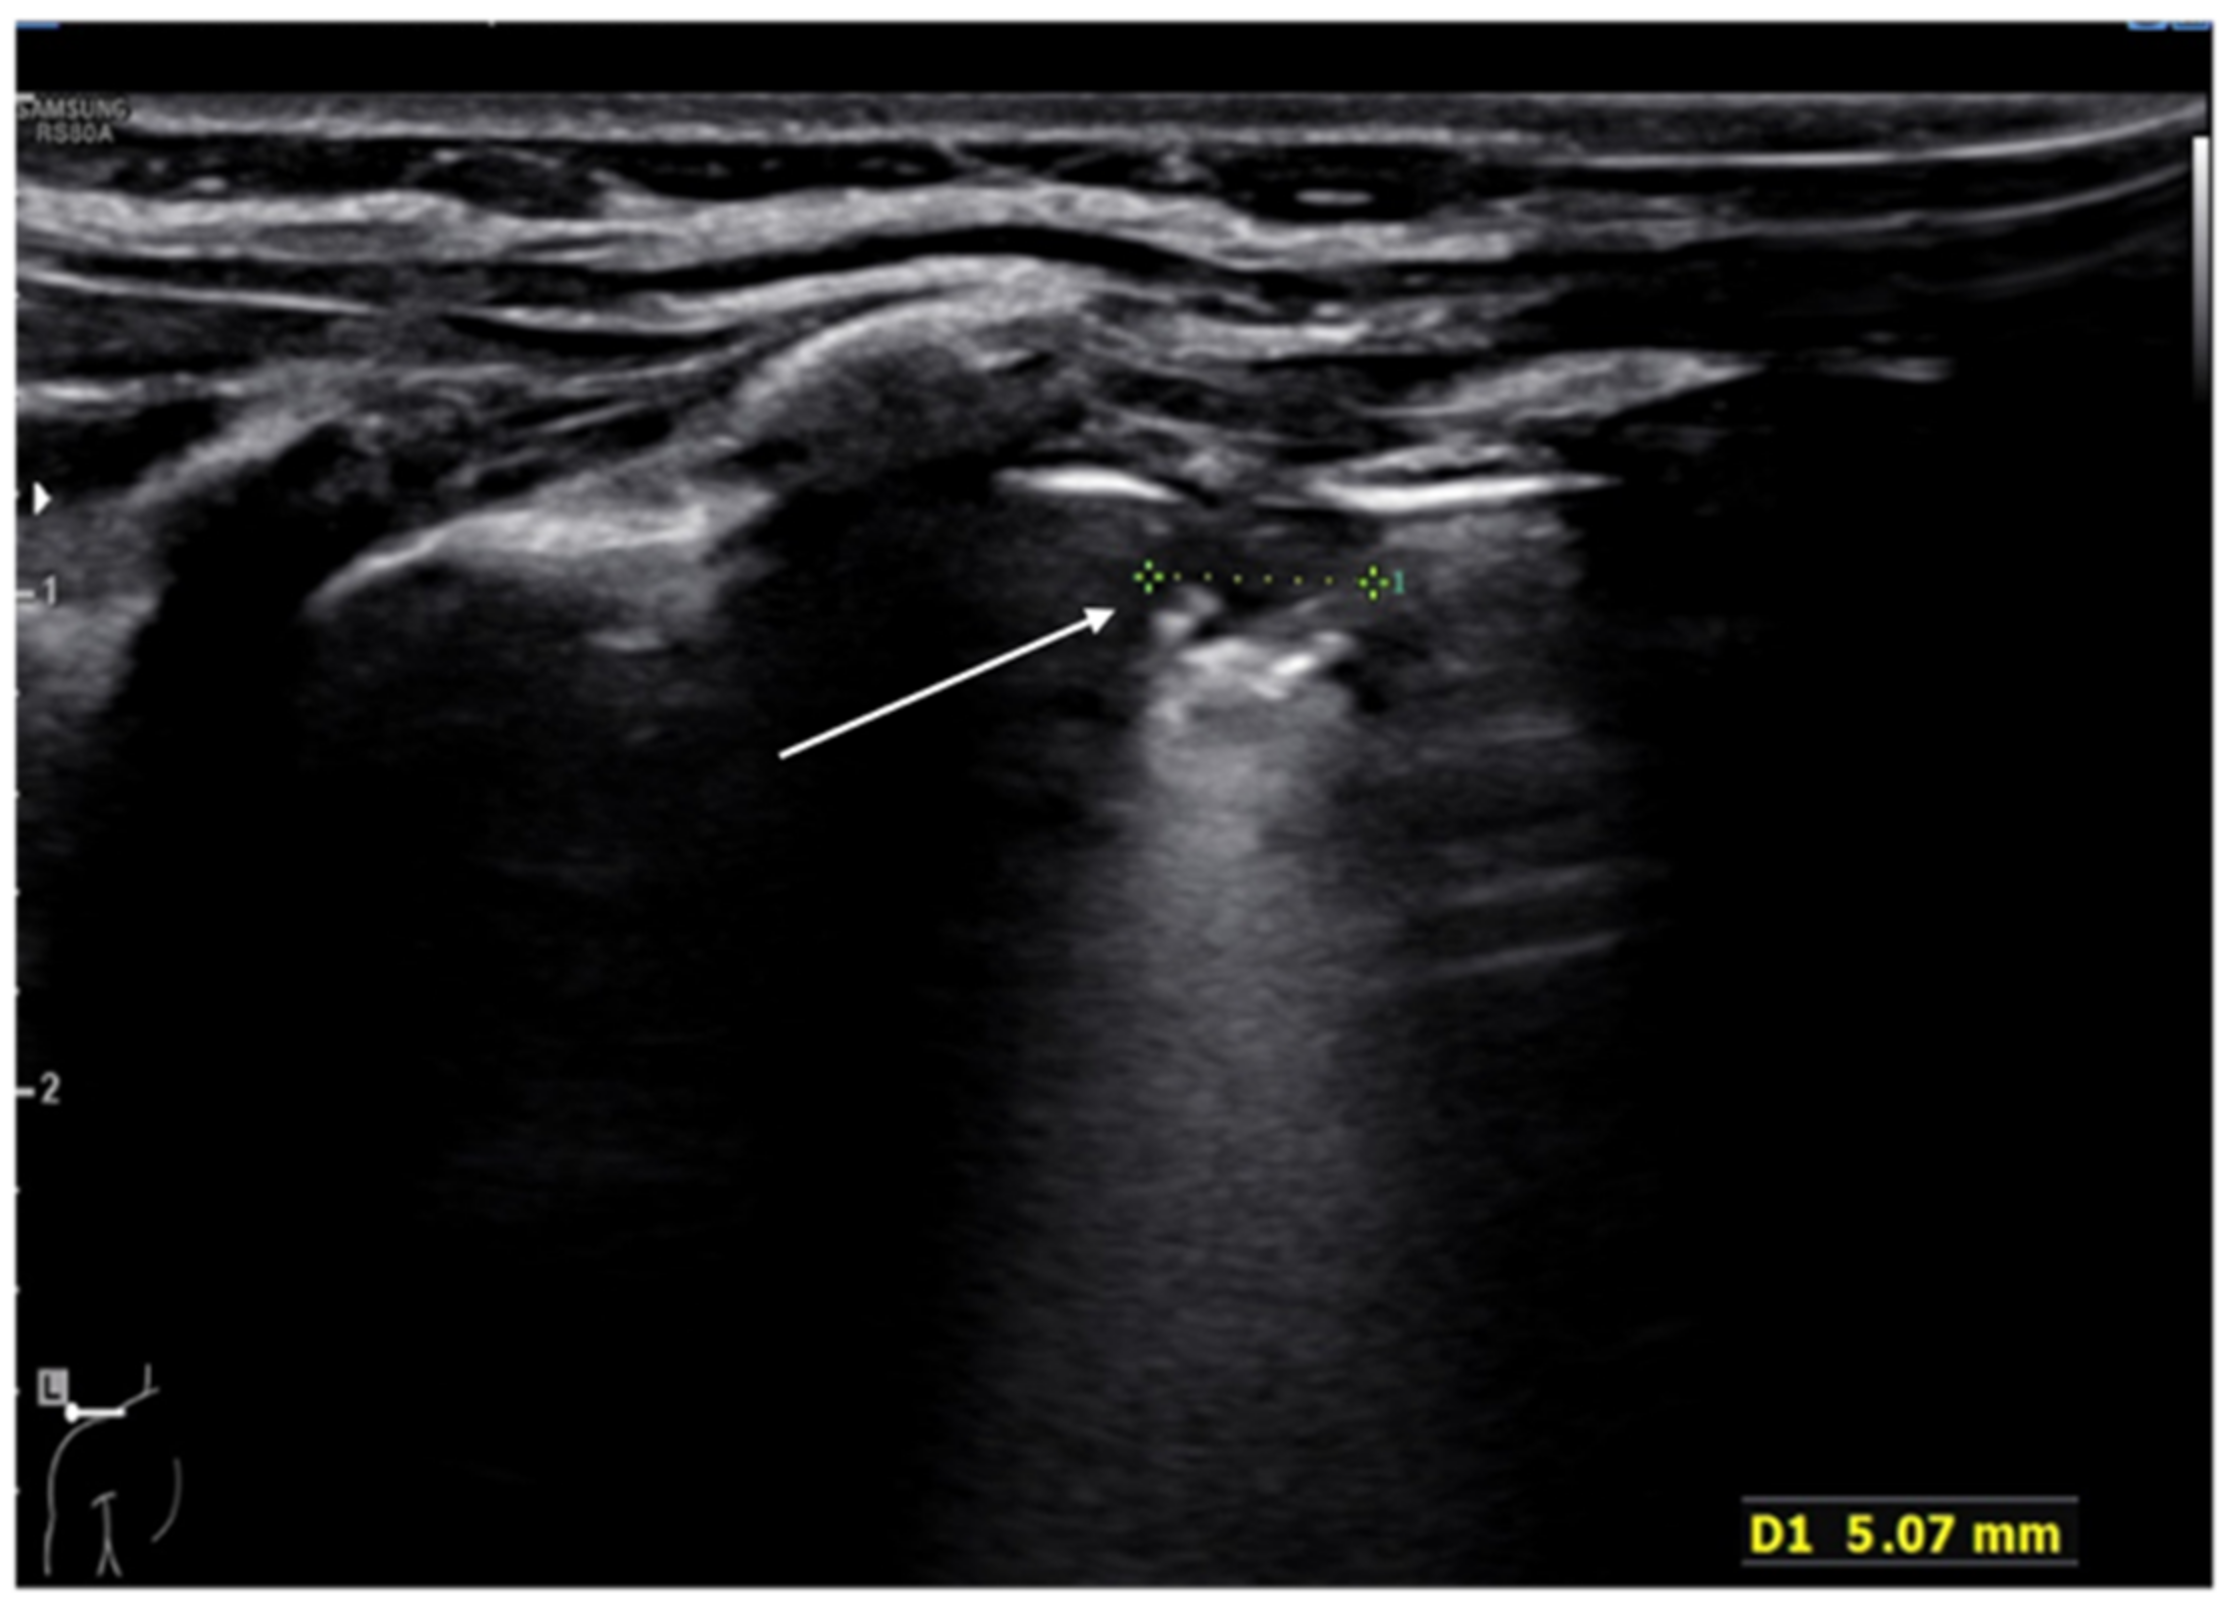

8. Pneumothorax, Pleural Effusion Empyema and Lung Abscess

- Kraft, C.; Lasure, B.; Sharon, M.; Patel, P.; Minardi, J. Pediatric Lung Abscess Immediate Diagnosis by Point-of-Care Ultrasound. Pediatr. Emerg. Care 2018, 34, 447–449. [Google Scholar] [CrossRef]

- Lin, F.; Chou, C.; Chang, S. Differentiating pyopneumothorax and peripheral lung abscess: Chest ultrasonography. Am. J. Med. Sci. 2004, 327, 330–335. [Google Scholar] [CrossRef]

- Chen, H.J.; Yu, Y.H.; Tu, C.Y.; Chen, C.H.; Hsia, T.C.; Tsai, K.D.; Shih, C.M.; Hsu, W.H. Ultrasound in peripheral pulmonary air-fluid lesions. Color doppler imaging as an aid in differentiating empyema and abscess. Chest 2009, 135, 1426–1432. [Google Scholar] [CrossRef] [PubMed] [Green Version]